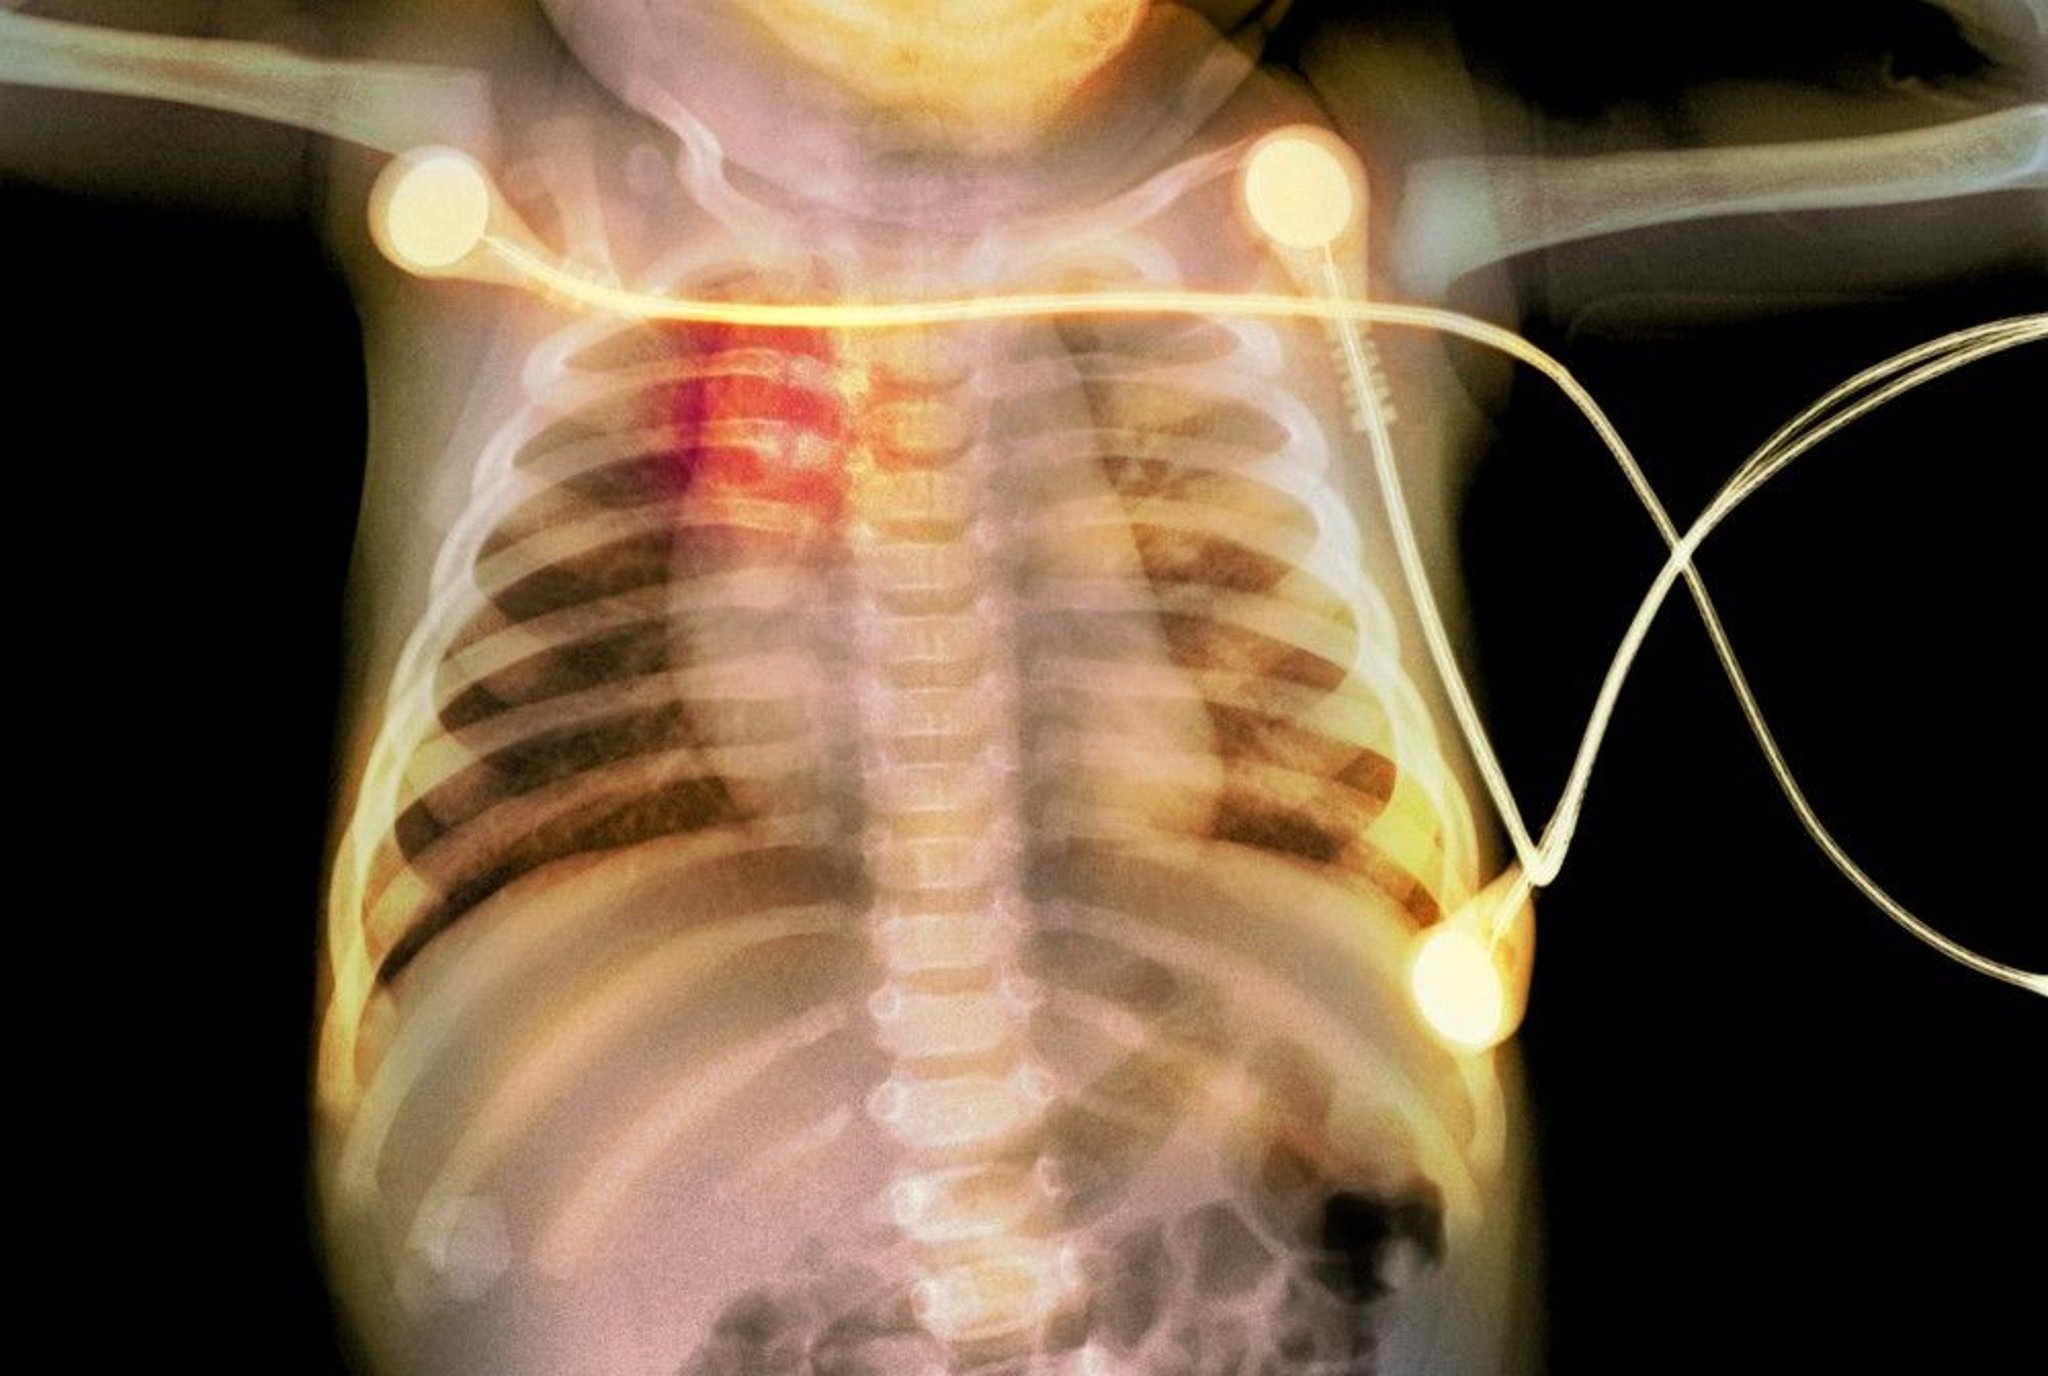

This radiograph shows rib fractures (highlighted in red) in an infant, suggestive of child abuse.

PHOTOSTOCK-ISRAEL/SCIENCE PHOTO LIBRARY